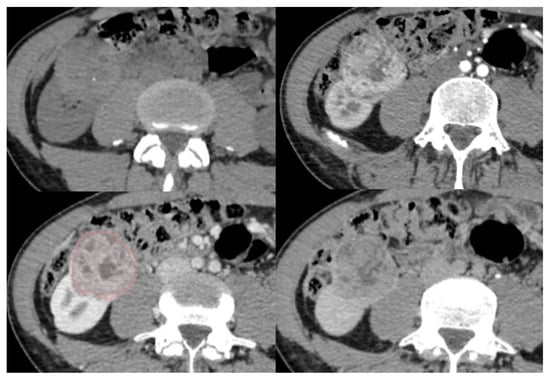

Figure 1. Representative case of segmentation for a papillary renal cell carcinoma (pRCC). A 68-year-old female with a pRCC. Unenhanced CT images (upper left), arterial phase (upper right), nephrographic time (lower left) and excretory phase (lower right) show a well-defined, demarcated, with heterogenous enhancement. Yellow outlined drawing represents segmentation margins.